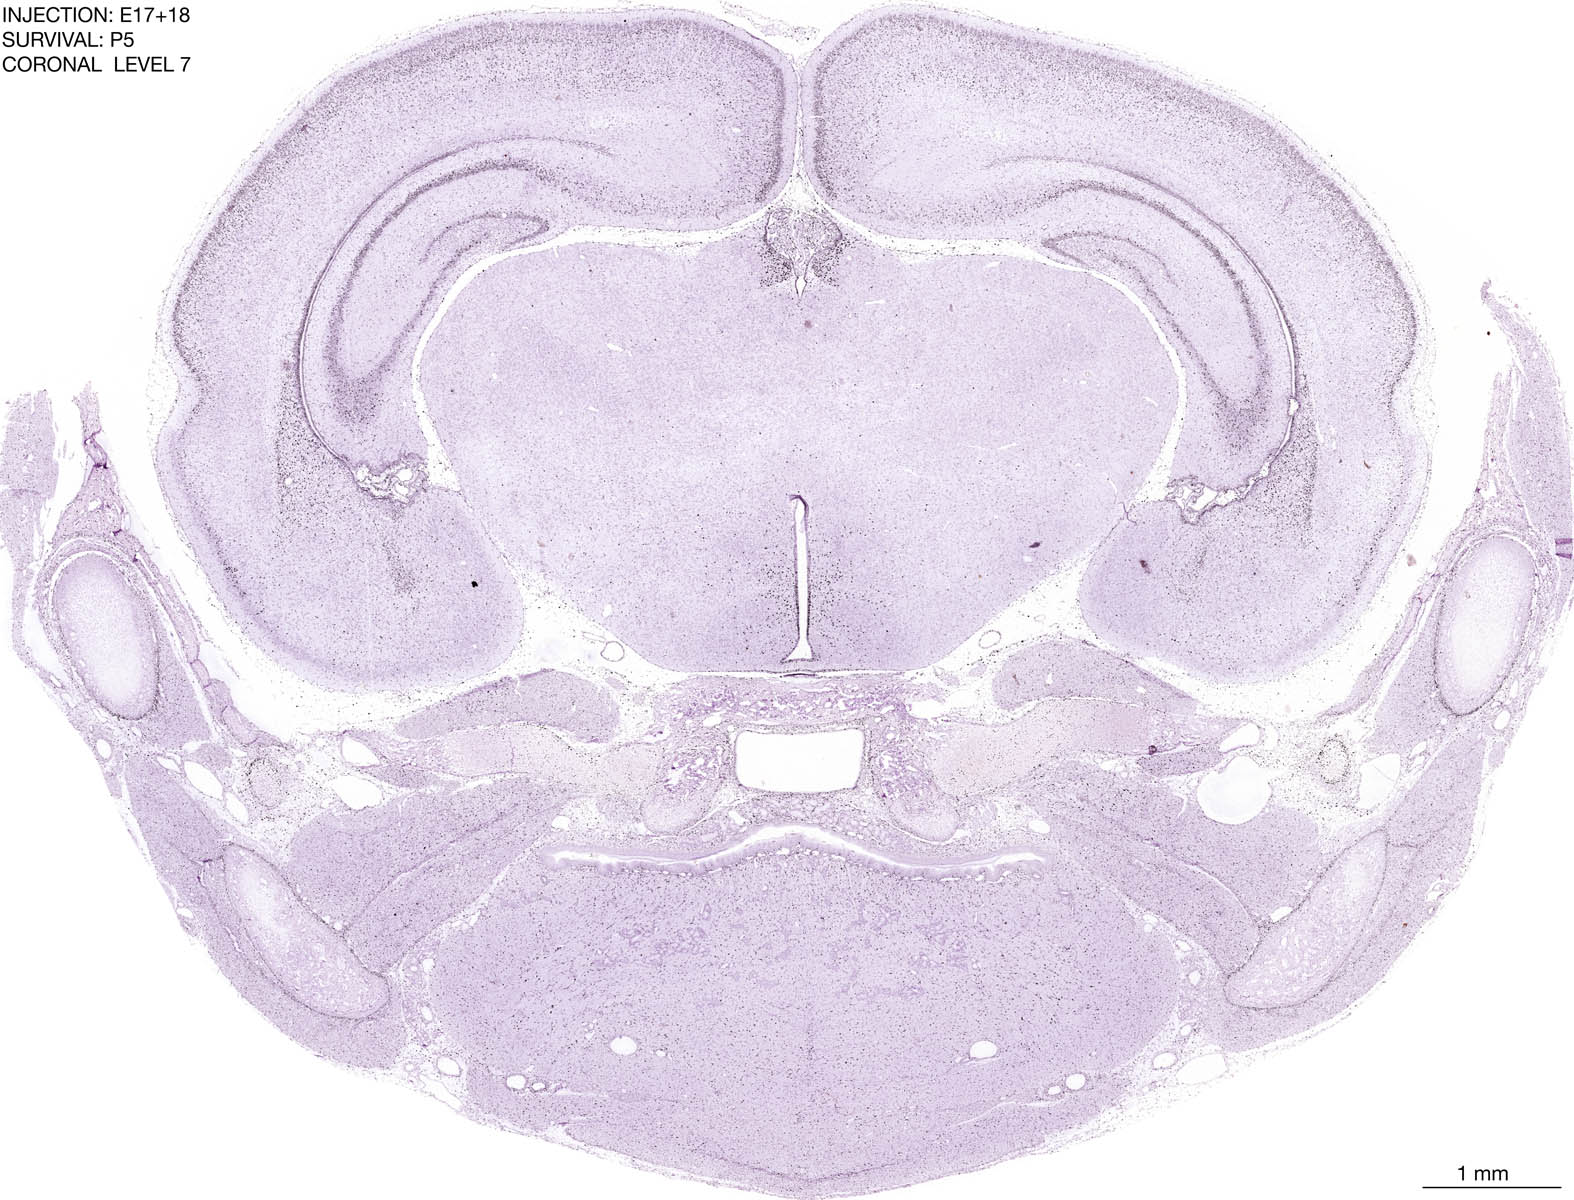

E17+18 P5 Survival The images below are from the brain of a rat that was exposed to tritiated thymidine on E17+18 and survived to P5. Download: Large | High Res Download: Large | High Res Download: Large | High Res Download: Large | High Res Download: Large | High Res Download: Large | High Res Download: Large | High Res Download: Large | High Res Download: Large | High Res Download: Large | High Res Download: Large | High Res Download: Large | High Res Download: Large | High Res Download: Large | High Res Download: Large | High Res Download: Large | High Res Download: Large | High Res Download: Large | High Res Download: Large | High Res Download: Large | High Res Download: Large | High Res Download: Large | High Res Download: Large | High Res Download: Large | High Res Download: Large | High Res Download: Large | High Res